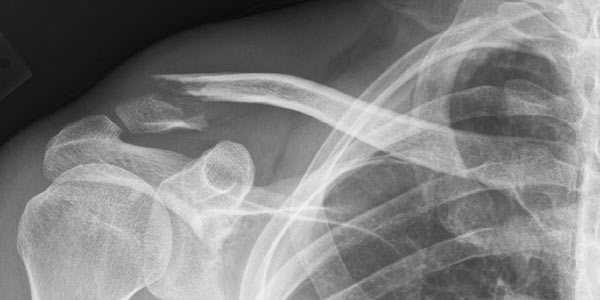

Como saber se é uma fratura? Fazendo uma radiografia do local. Como saber se precisa ir ao pronto-socorro para fazer uma radiografia? Para começo de conversa, a regra é que uma pessoa que sofreu uma fratura vai sentir muita dor no local, muitas vezes só de apalpar ou encostar nele. Também vai ter dificuldade em mover a área. Pode acontecer inchaço e até mesmo deformidade, dependendo da intensidade da fratura. Também podem ser vistos hematomas e,em um caso mais aterrorizante, que é a fratura exposta, onde o osso se rompe e se desloca, rasgando a pele e ficando exposto. Então, se houve algum trauma no local, se há dor, se há alguma limitação de movimento, vale a pena conferir o que está acontecendo.

O ideal em qualquer caso é que se procure imediatamente um pronto-socorro ortopédico, onde a fratura vai ser constatada através de uma radiografia e o membro vai ser imobilizado da forma correta, para que sua cicatrização não deixe sequelas e não comprometa sua funcionalidade. A imobilização pode ser feita de várias formas, desde o bom e velho gesso, até imobilizadores removíveis. A ressalva que eu faço é que não deixe que imobilizem o membro de forma muito apertada, pois a tendência é que ele inche nos dois primeiros dias e isso pode te obrigar a voltar no pronto-socorro para trocar a imobilização que comprimirá a área. Digo isto porque nem sempre é o médico quem engessa e nem sempre a pessoa que o faz tem conhecimento ou cuidado de lembrar que o membro pode inchar. Já aconteceu comigo de ter que trocar o gesso no meio da madrugada porque o colocaram muito justo e a área inchou, comprimindo meu braço.